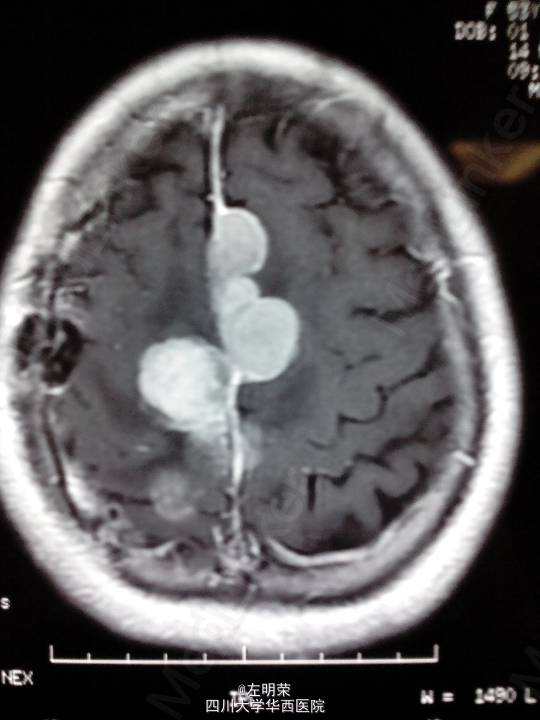

脑膜瘤术后复发(多发脑膜瘤)

左下肢乏力伴间断抽搐半年+, 患者于5年前行左侧额叶脑膜瘤切除术,术后行伽马刀治疗数次,近来出现肢体无力伴抽搐,不规律服用抗癫痫药物,昨日再发抽搐。

1、多发脑膜瘤 2、继发性癫痫

行占位切除术;待病理结果;术后应复查头部MRI,确定肿瘤切除情况,拟定下一步治疗方案。